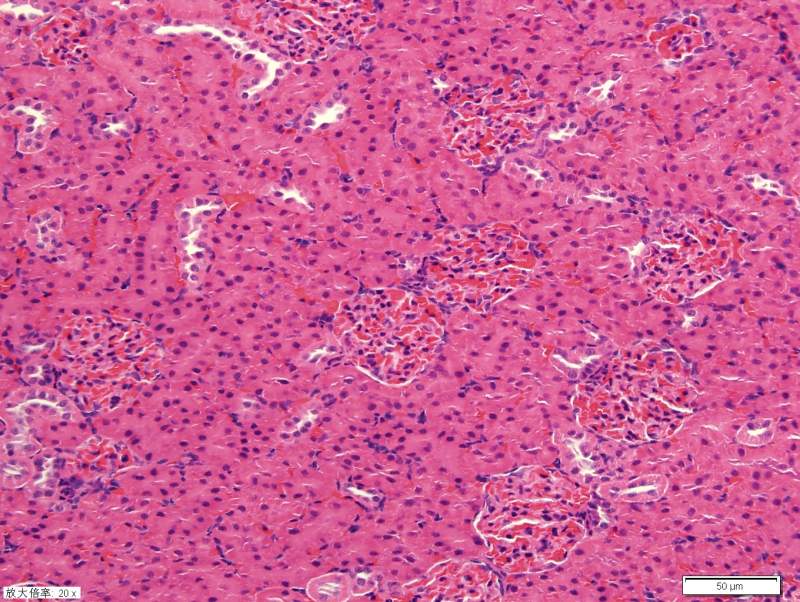

请教各位高手关于肾脏HE染色 已有1人参与